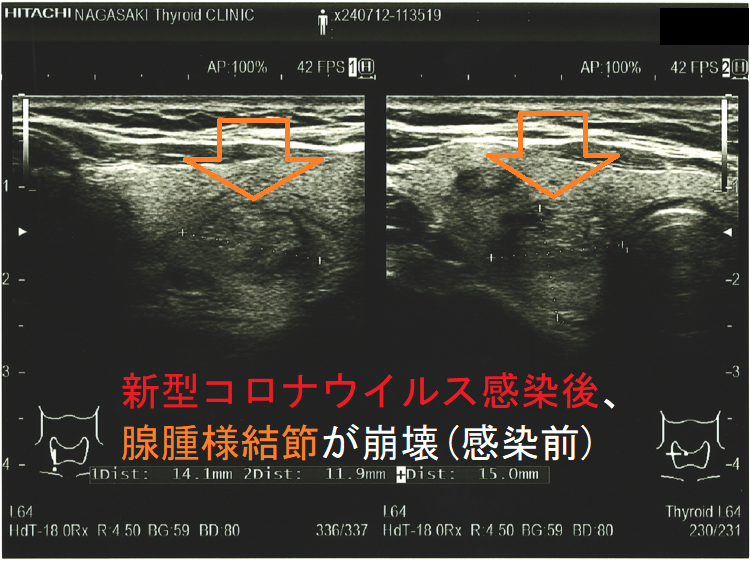

新型コロナウイルス感染(COVID-19)後、腺腫様結節が崩壊(感染後);感染後、内部は崩壊し、亀裂部に液体が充満。のう胞型腺腫様結節(嚢胞型腺腫様結節)のようになってしまった。